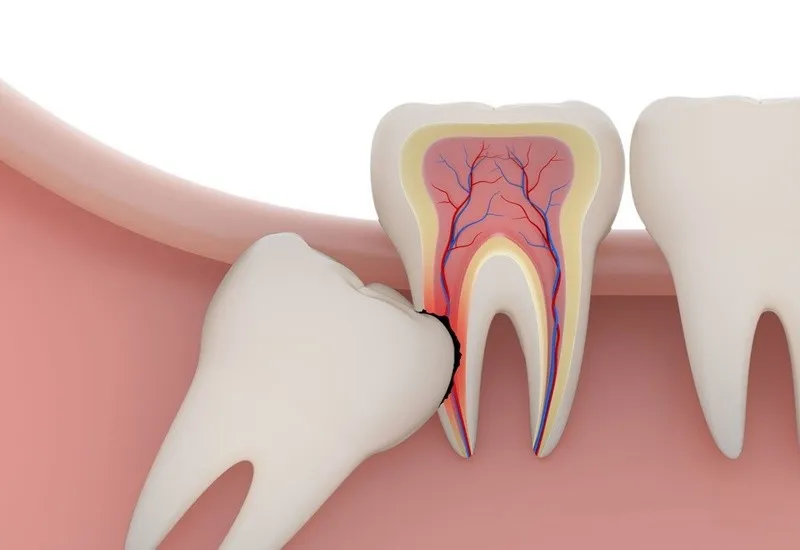

Nhổ răng số 8, còn được gọi là nhổ răng khôn, là một thủ thuật nha khoa nhằm loại bỏ một hoặc nhiều chiếc răng hàm thứ ba. Đây là các răng vĩnh viễn mọc ở vị trí cuối cùng của hàm trên và hàm dưới. Lúc này những răng khôn không có đủ không gian để mọc hoàn chỉnh. Vì thế chúng có thể gây ra đau đớn, viêm nhiễm bề mặt lợi và răng. Thậm chí dẫn đến những vấn đề nghiêm trọng về sức khỏe răng miệng. Trong trường hợp này, việc nhổ bỏ răng khôn là cần thiết để ngăn ngừa các biến chứng.

- Răng bị sâu, viêm nhiễm, viêm nha chu, hoặc tình trạng chảy máu nướu kéo dài. Từ đó tạo điều kiện thuận lợi cho vi khuẩn phát triển.

- Vi khuẩn có thể lan rộng, ảnh hưởng đến các răng kế cận. Cũng như các cấu trúc quanh răng như tủy răng, xương hàm và dây thần kinh.

- Răng mọc lệch, mọc ngầm hoặc mọc ngang dẫn đến tình trạng chen chúc. Từ đó làm xô lệch toàn bộ hàm răng, gây mất cân đối khớp cắn và ảnh hưởng thẩm mỹ.

- Răng số 8 mọc chèn ép vào dây thần kinh dưới nướu. Theo thời gian chúng = có thể gây tổn thương nghiêm trọng. Tình trạng này dẫn đến giảm hoặc mất cảm giác ở vùng niêm mạc miệng, môi, da. Thậm chí có thể ảnh hưởng đến vùng thái dương hoặc gây đau đầu kéo dài.